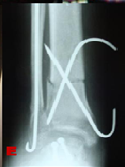

Treatment of Talar Body Fractures with Closed Reduction and Percutaneous Fixation

Reda Hussein El-Kady*,Mohammed AbdelFattah Sebae